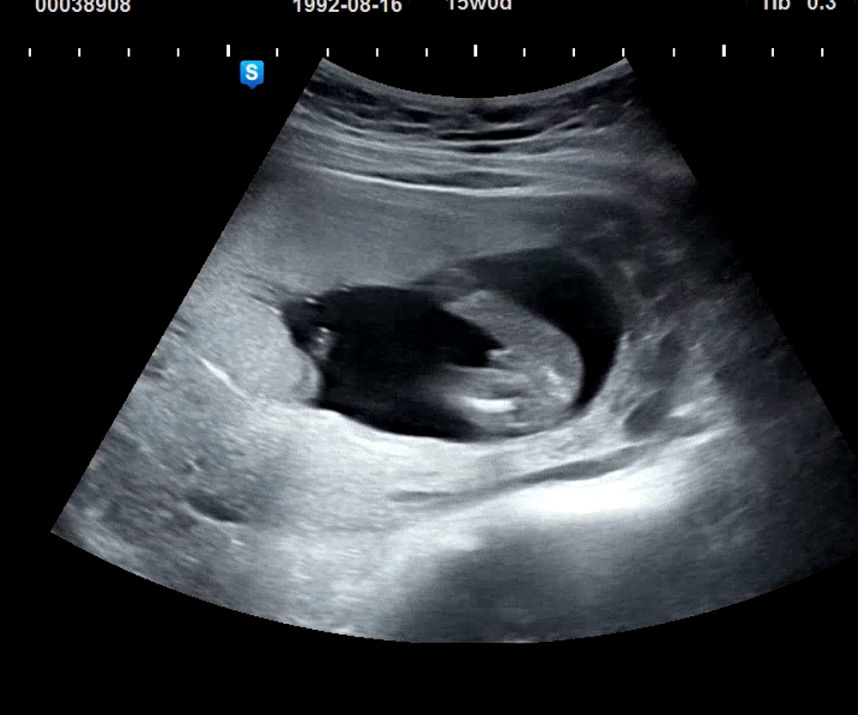

ㅋㅋㅋ선생님께 반전은 없겠죠..? 했더니 15주에 이정도 존재감이면 좀 힘들죠.. 라고 ㅋㅋㅋㅋㅋㅋㅋㅋ 아들맘 확정받고왔어여.!! ㅋㅋㅋ 딸을원하긴했지만 저 거튜를 보니 귀엽고 건강하다니 넘 기분좋네요 ㅎㅎㅎ

ㅋㅋㅋ선생님이 이왕 아들일꺼면 대물이낫잖아여 이랴서 빵터졌어요 ㅋㅋㅋㅋ